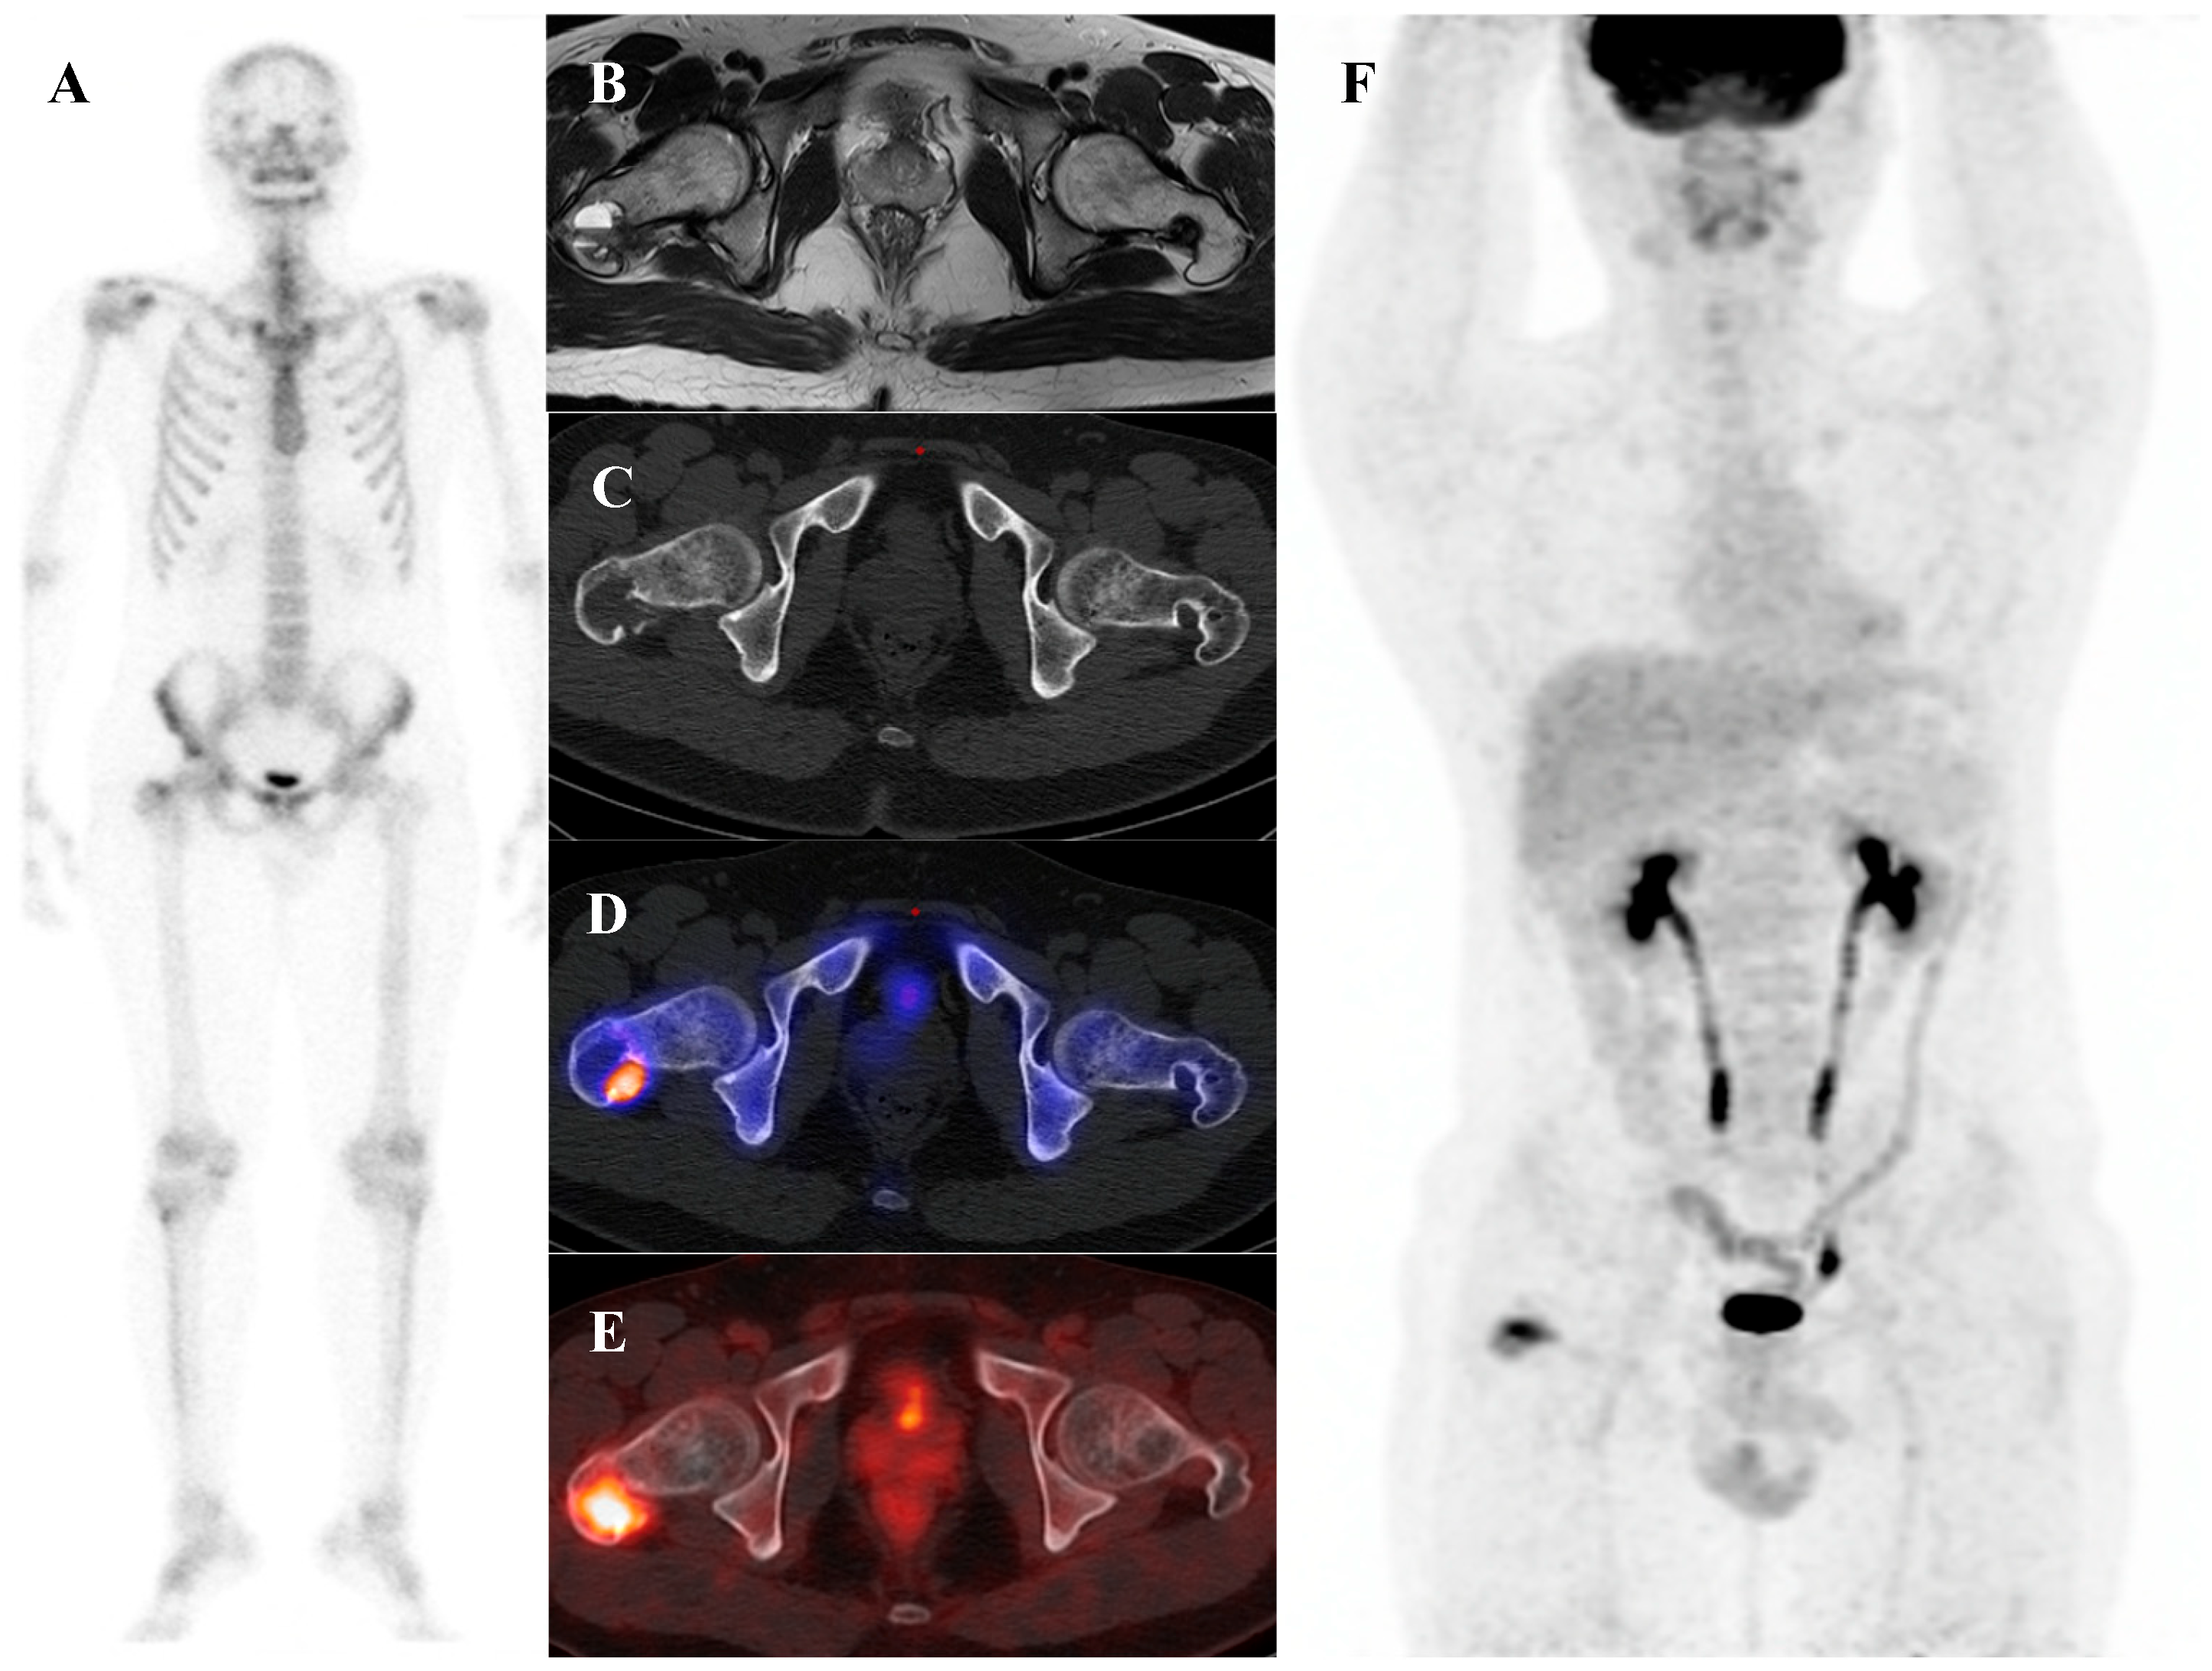

Patients with Ewing sarcoma are at high risk for disease recurrence, which most often occurs in the lungs or bone and carries a poor prognosis [45,46]. [18F]FDG PET/CT is an extremely valuable tool for post-treatment surveillance and for the early detection of recurrent disease [18,25]. The appearance of new, focal [18F]FDG-avid lesions on follow-up scans is highly suspicious for recurrence and prompts further investigation and salvage therapy. Whole-body nature of [18F]FDG PET/CT is ideal for detecting recurrence at any potential site. Figure 2 demonstrates a representative case in which bone scintigraphy failed to reveal recurrent disease, whereas [18F]FDG PET/CT clearly identified the metabolically active presacral mass, subsequently confirmed as recurrent Ewing sarcoma after surgical excision.

Figure 2.

A 19-year-old female with recurrent Ewing’s sarcoma. (A,B) Bone scintigraphy shows no abnormal uptake on both anterior and posterior view. (C) T1 fat-suppressed magnetic resonance imaging demonstrates a lobulated, enhancing presacral mass with invasion of the sacrum. (D–F) [18F]FDG positron emission tomography/computed tomography reveals intense uptake of the mass (SUVmax 9.0). Surgical excision confirmed recurrence of Ewing’s sarcoma.